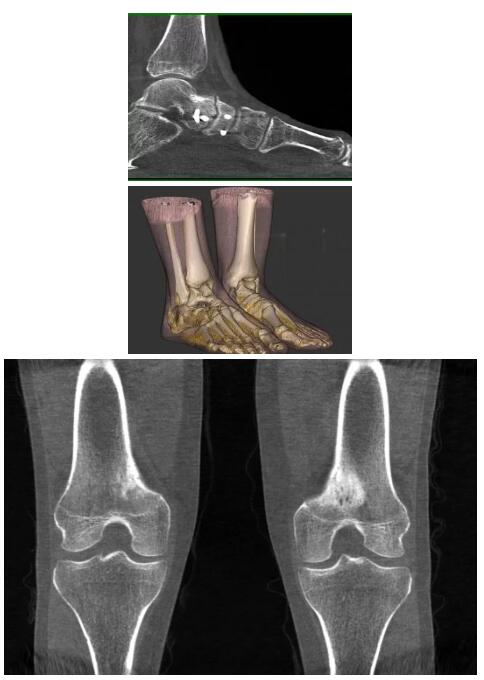

另外一款被稱為世界上最小的CT,它的重量?jī)H300磅,不僅能夠掃查足部,還可以檢查膝蓋和上肢等。

與上面介紹的CT一樣,它同樣具有輻射低、占地空間小(23*36)的特點(diǎn),隨開(kāi)隨用(支持直接接入墻上的插座)。

這款CT使用非常方便,通過(guò)上下移動(dòng)保持與患者的手臂或者雙腿齊平,掃描快速,僅需要30秒左右就可以完成掃查。

以上介紹的CT均來(lái)自國(guó)外同一家公司,這些CT均配置了可視化軟件,可以進(jìn)行切片、3D重建以及大型CT附帶的所有典型的操作功能。

以下是這些“特立獨(dú)行”的CT所拍出來(lái)的圖像: